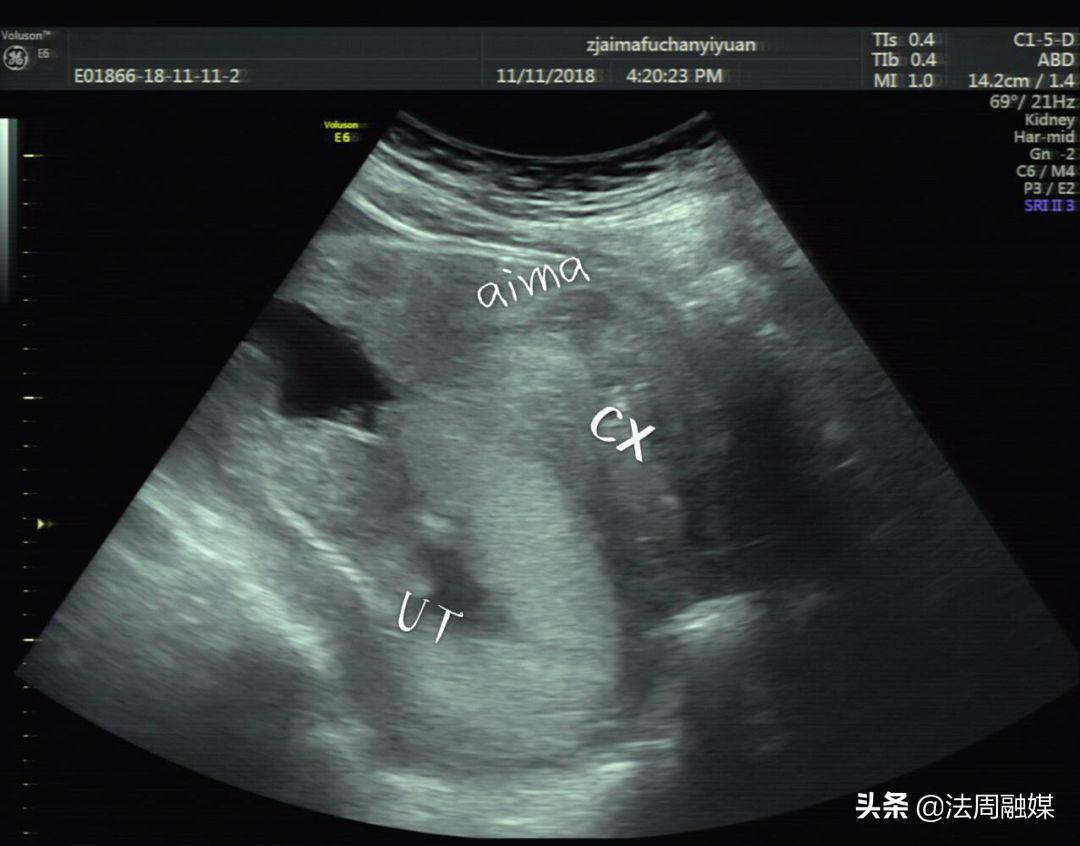

膀胱明显充盈表现细长,后方见妊娠子宫回声

子宫明显后倾后屈,宫颈细长

尿潴留缓解,子宫位置已转前位,宫颈远离尿道